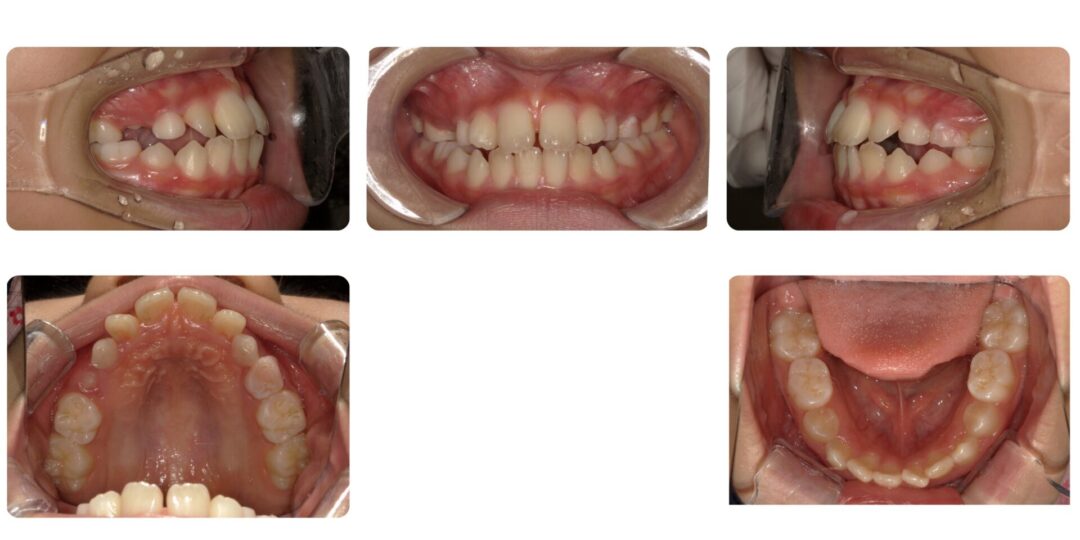

歯槽性上下顎前突|初診時10歳

矯正治療前

ご相談内容

前歯上下ガタガタ

治療内容

第一期治療 上顎タングガード付き拡大床による歯列矯正

治療期間

1年4ヶ月